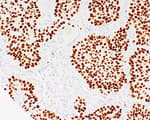

Mouse anti-Progesterone Receptor Monoclonal Antibody [188]

Bethyl Laboratories Catalog # A500-025A A500-025A-T

ValidatedDocuments (7)Mouse anti-Progesterone Receptor Monoclonal Antibody [188]

Validation Performed

All Bethyl Laboratories® antibodies are validated to meet our strict performance standards.

Target: Progesterone Receptor

Reactivity: Human

Applications:

Platforms: COMET™

Host: Mouse

Conjugate:

Purity:

For ordering information, see our International Distributors

Product has been discontinued